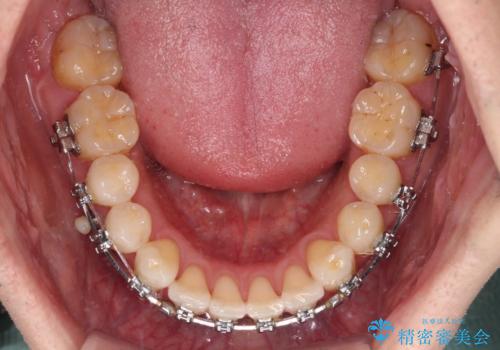

- 以前矯正治療を行ったものの、思い通りの仕上がりではなく、更には後戻りが気になってきたとのことで来院された患者様です。

上顎右側の第一小臼歯が動きにくい歯であり、以前矯正治療を行った際に傾斜した位置のまま終了したことと、それに伴い後戻りで歯列が波打っているようになっていることを大変気にしていらっしゃいました。

咬合平面改善のため、アンカースクリューを多用し、ワイヤー装置にて矯正治療を行うこととしました。

動きにくい歯はやはり動きにくく、咬み合わせ改善に時間を要しましたが、患者様には大変満足していただけました。